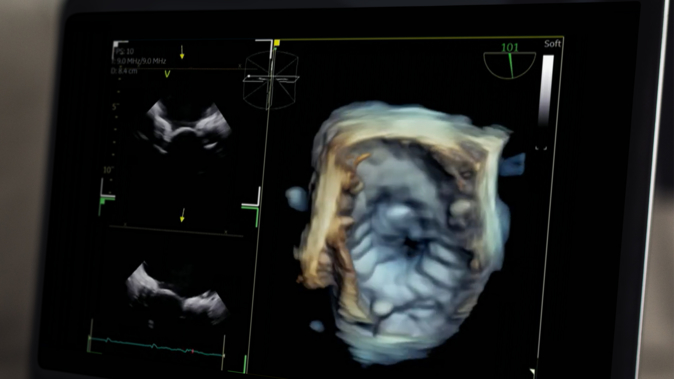

Innovation for transcatheter tricuspid interventions - LIVE case

24 Nov 2024 – From PCR London Valves 2024

Dive into the world of innovation for transcatheter tricuspid interventions. Discuss the remaining challenges associated with currently available options, capture the central role of imaging guidance, and understand the anatomical selection criteria for transcatheter tricuspid valve replacement. Experience a live case from St. Thomas' Hospital, London,...